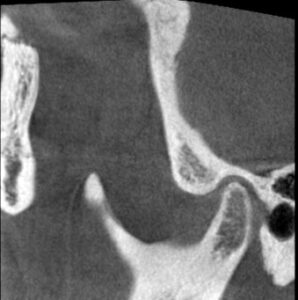

この状態のこの方の顎の関節のCTスキャンです。

左側の関節です。

関節の隙間が少なく、関節を圧迫していますから

つまり先にお見せした

動画と同じ状態ということです。

口が開くときも閉まるときも軟骨が外れて音がする。

まさにこの状態ということです。

この状態になった時のこの患者さんのCTスキャンの比較はこちらです。

治療前 左側

関節圧迫が取れているのがわかるでしょうか?

これが治療後の状態です。

赤い線は耳の穴です。

顎関節は耳の穴の裏側に位置します。

耳の穴を関節が圧迫していたらどうなりますか?